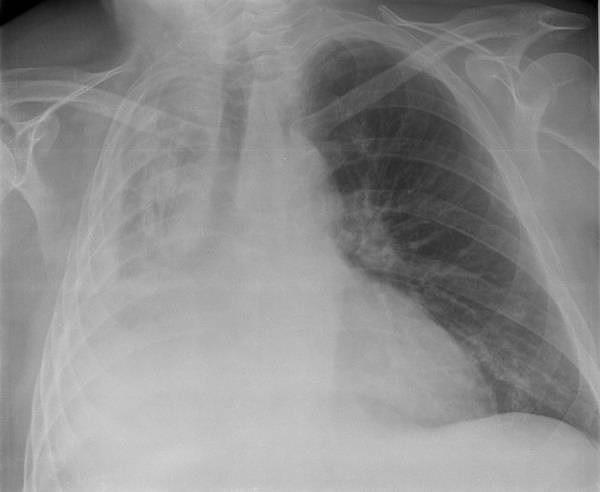

| Hình chụp X-quang của một người bị sụp phổi. Ảnh: SCMP. |

Tràn khí màng phổi là khi có một lượng không khí bất thường trong khoang màng phổi giữa phổi và thành ngực. Các triệu chứng thường bao gồm đột ngột đau nhói, đau một bên ngực và khó thở.